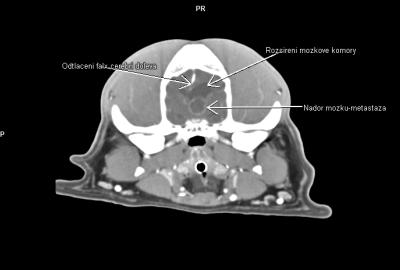

• primární a metastatické nádory mozku a mozkových plen,

V regionu hrtanu jednoznačně vedou nádory štítné žlázy(thyreoidey). Často se jedná o zhoubné varianty (karcinomy) s lokální invazivitou do struktur hrtanu a jazylky, s tendencí k tvorbě metastáz-mediastinum, plíce. Patří ale zároveň k nádorům poměrně často operovatelným. CT pak hraje v takovýchto případech zásadní diagnostickou roli.